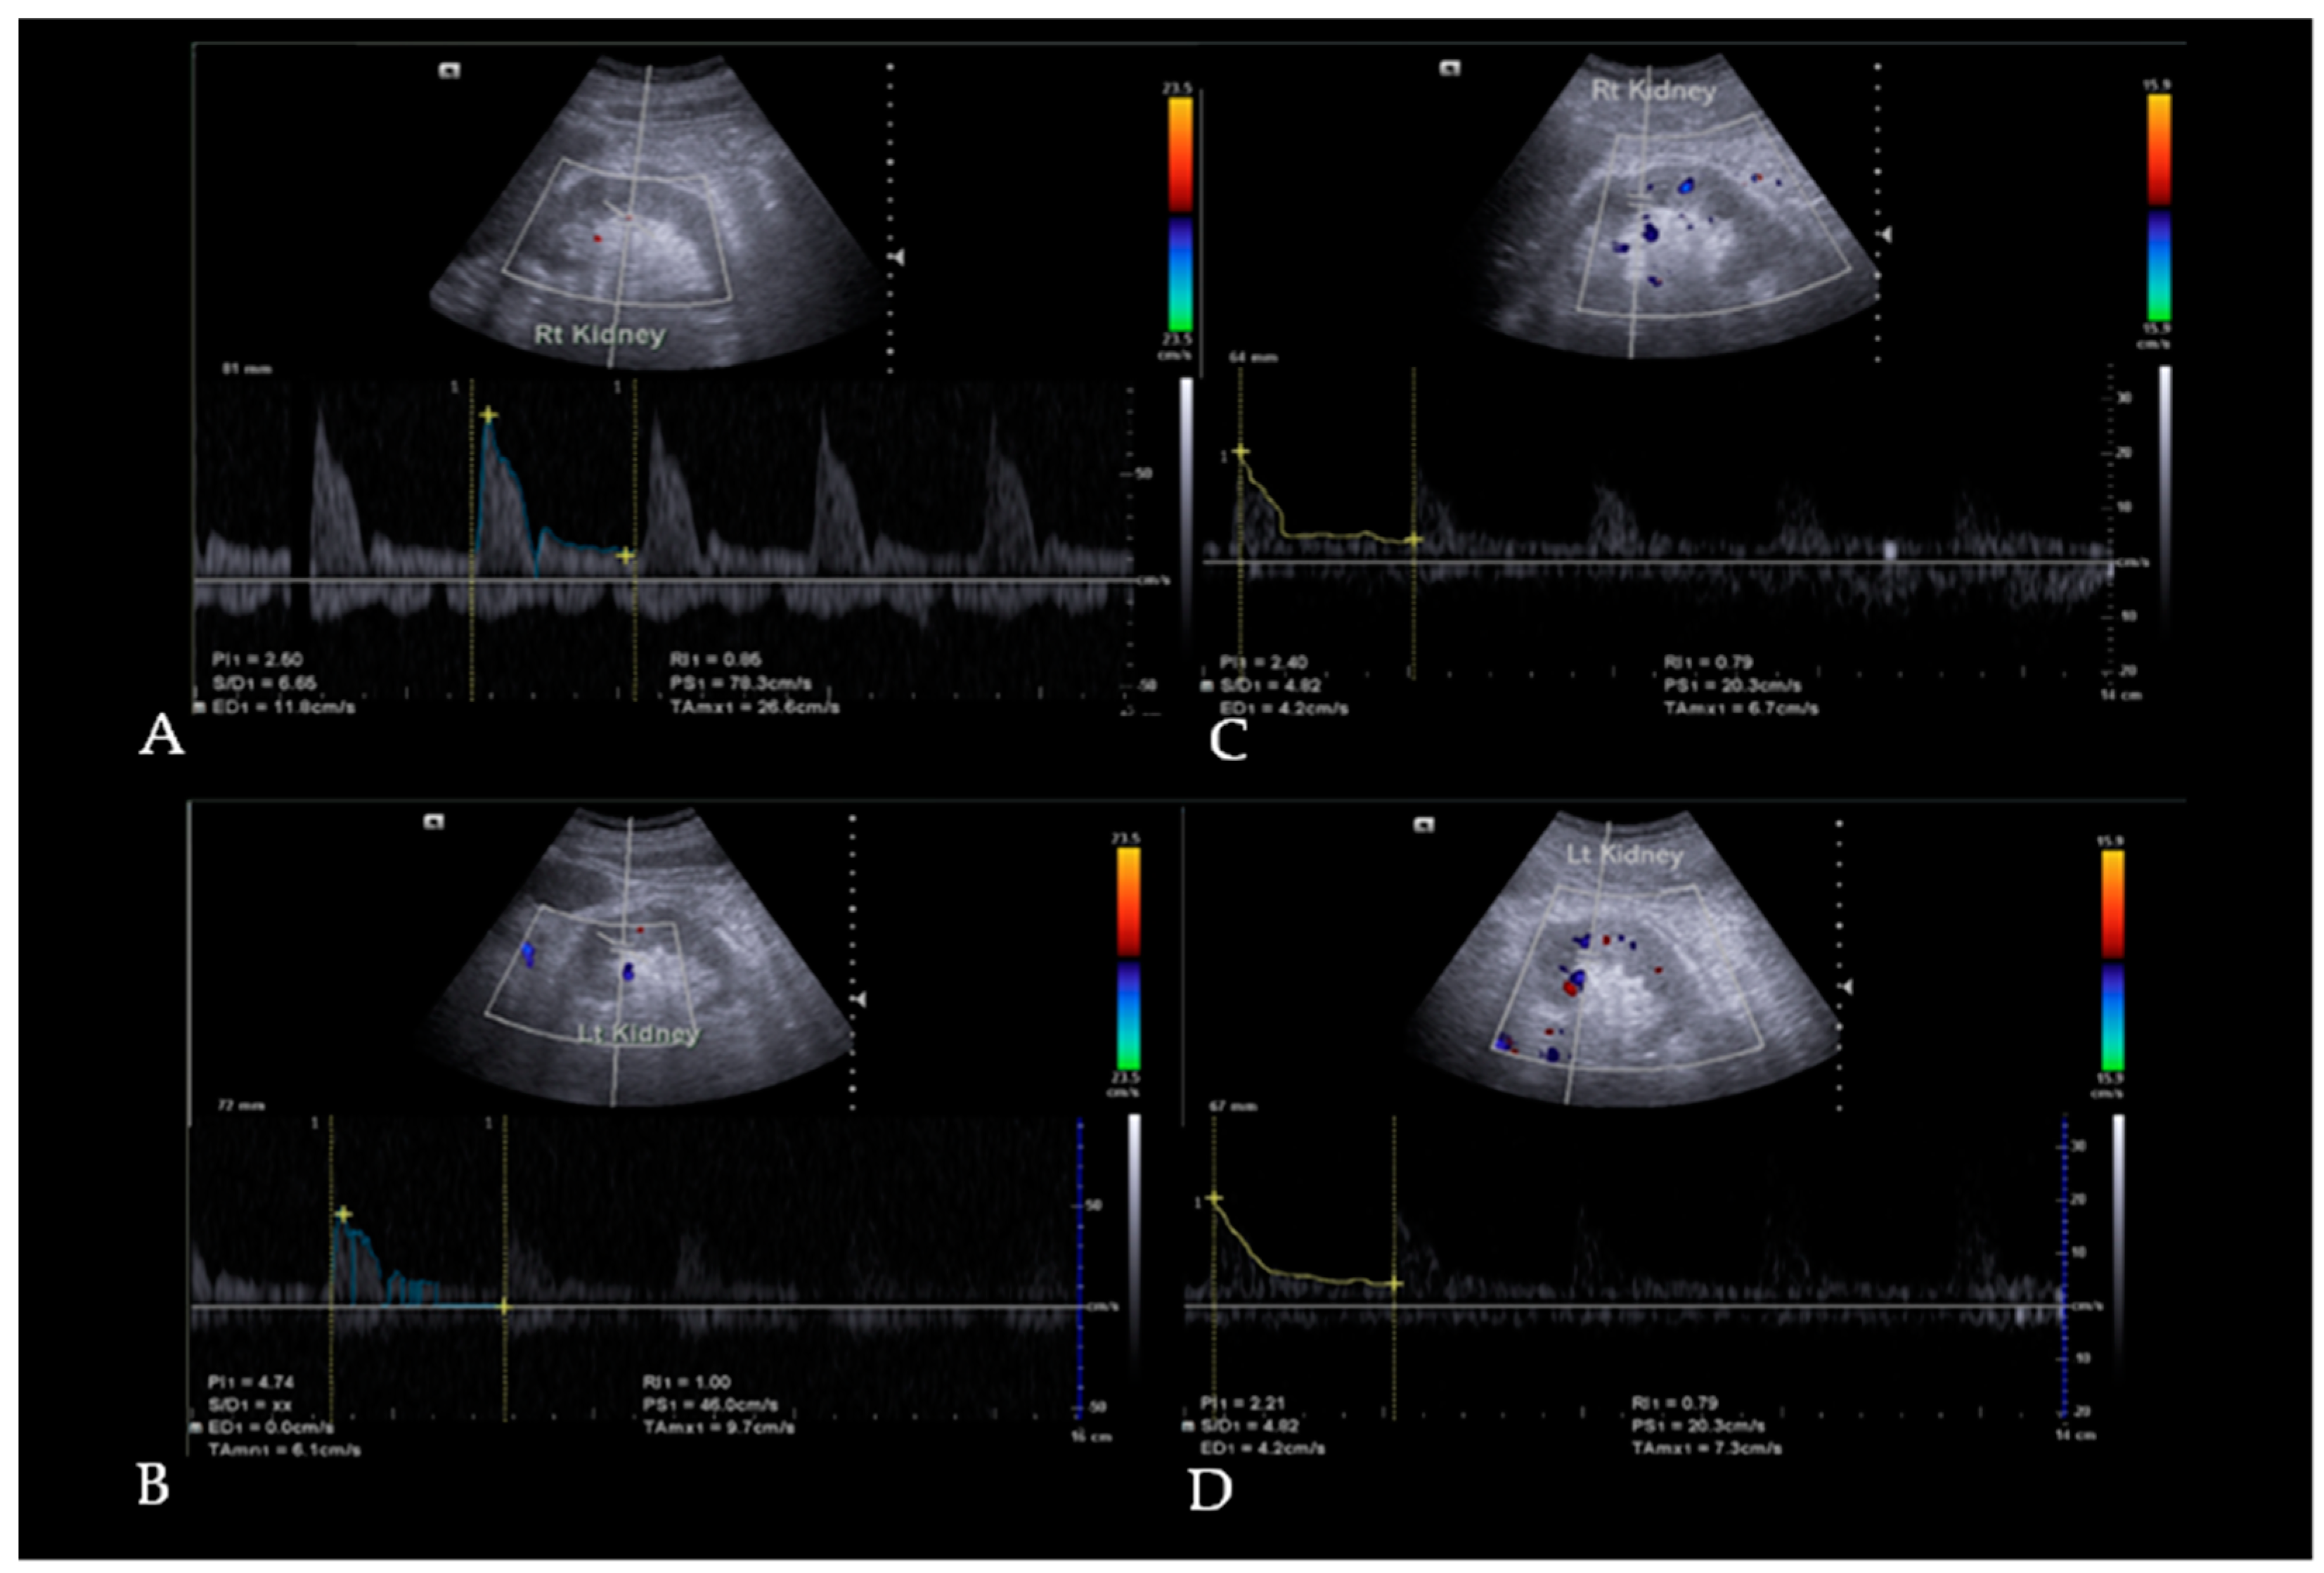

2.5. Doppler Ultrasound Examination

3.2. Resistive Index (RI) and Pulsatility Index (PI) Changes